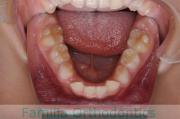

No.22V-299

- 上顎前突

- 叢生

- 30歳

- 女性

上の出っ歯、口が閉じにくい、下の前歯のガタガタを治したいということで来院されました。上顎から左右小臼歯を、下の前歯は凹凸が非常に強いので、こちらから一本抜歯を行いました。2年強、30回程度の通院が必要でした。

成人になってからの叢生(でこぼこ、凹凸、ガタガタ)は、保定をしっかりしないと後戻りをしてしまうリスクが高いです。